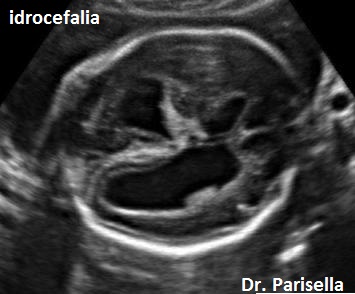

Idrocefalo X-Linked da Stenosi dell'Acquedotto di Silvio (HSAS) OMIM 307000

E' la più comune forma di idrocefalo ereditario, legato a mutazioni del gene L1CAM che mappa in Xq28. Caratteristicamente presenta idrocefalia e pollici addotti. L'idrocefalia è legata a stenosi dell'acquedotto di Silvio ed è quindi di tipo triventricolare con interessamento dei ventricoli laterali e del terzo ventricolo. Possono essere presenti altre anomalie del SNC come l'ipoplasia del corpo calloso.